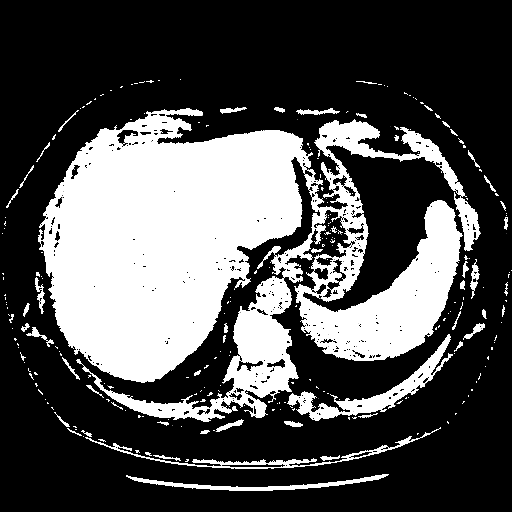

Generated VENOUS CT scan (A→B translation)

Full window (WL 1023.5, WW 4095 β†’ Low βˆ’1024, High +3071)

Actual HU range: [-1024.0, 3071.0]